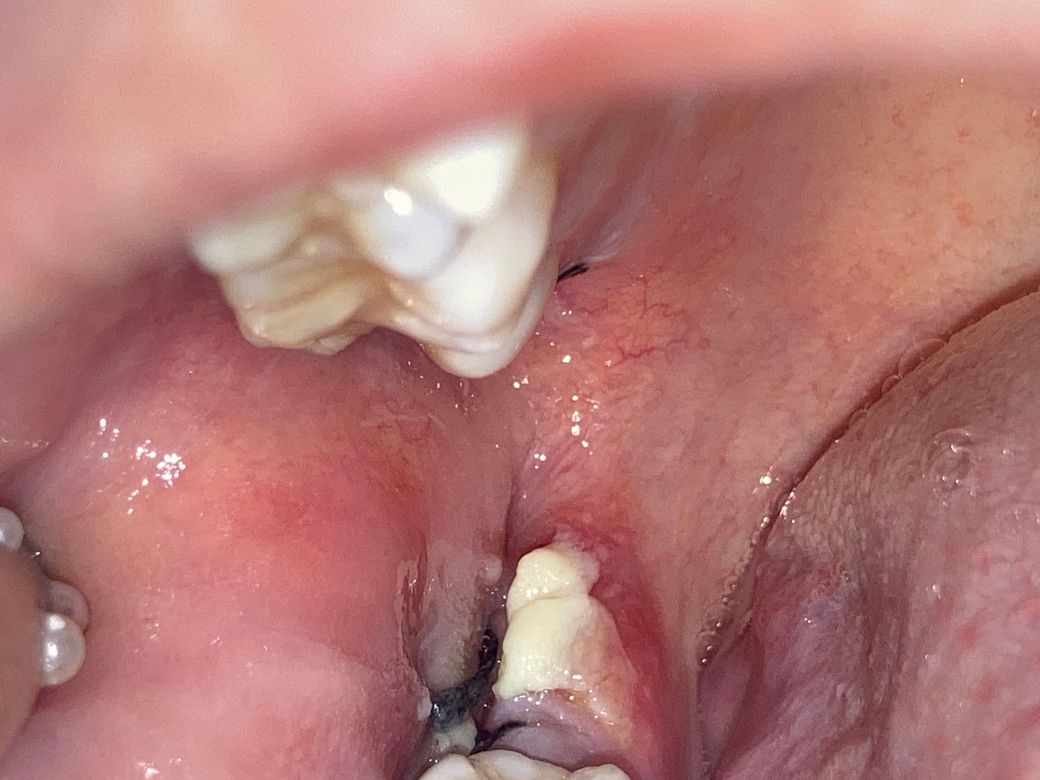

사랑니 발치 3일차 하얀덩어리의 존재?

이게 뭔지 알 수 있을까요 ㅜㅜ 위아래 동시에 뽑앗는데 아래에만 생겼어요 혹시 몰라서 제거 안했고 가글 열심히 했어요 약도 잘 챙겨먹구요 ㅜㅜ 다른 아빨 뺏을때는 이러지 않았어요

• 2번 째 사진